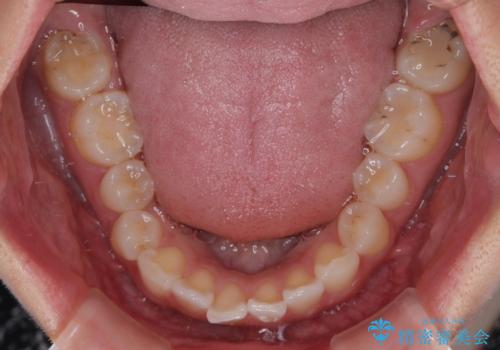

- 前歯のデコボコと突出感を気にして来院された患者様です。

極力目立たない装置を希望とのことで、インビザラインを用いて非抜歯で矯正治療を行うこととしました。

事前に親知らず2本を抜歯し、多少歯列を後方に移動できるように準備をした上で、なるべく歯と歯の間を削ることなくデコボコを解消できるように計画しました。

前歯の捻れを改善するとともに、口元が少しでも引っ込むように治療計画を立て、仕上げることができました。

長時間の装着を徹底し、遠方からの通院にもかかわらずしっかりと通院いただき、予想よりも早く治療を終えることができました。